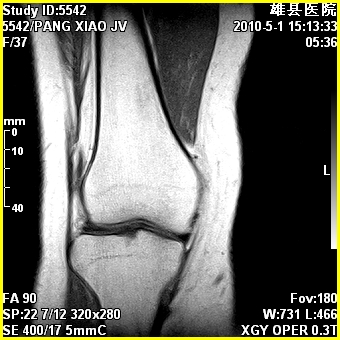

标题: MRI2894:患者右膝关节疼痛两月余,无明显外伤史 [打印本页]

标题: MRI2894:患者右膝关节疼痛两月余,无明显外伤史

右股骨下端前内侧类圆形异常信号,位于干骺端,呈长t1长t2改变,但信号不均,t1图上病灶中心见小片状稍高信号影,t2图上见散在稍低信号影,stir像呈高信号,因病灶较小,缺乏特征性改变,结合患者年龄及部位,考虑嗜酸性肉芽肿可能性大。胫骨关节面下的小囊状异常信号,如果一元论考虑则为嗜酸性肉芽肿,不过发生在这个部位的少见,二元论考虑为邻关节骨囊肿。半月板与前后交叉韧带均未见异常。

右股骨下端前内侧干骺端囊性良性病变,考虑 1内生软骨瘤 2骨囊肿 3肉芽肿。